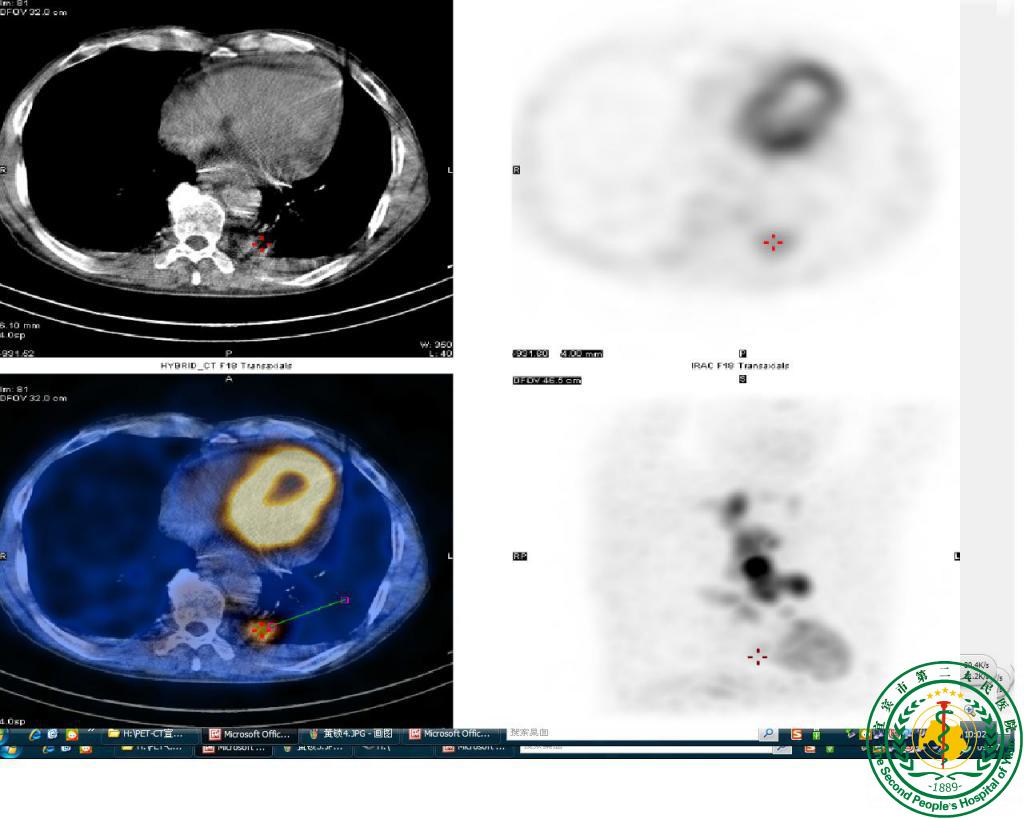

“鹰眼”派特CT确诊疑难“肺结节”一例

宜宾市第二人民医院 图文